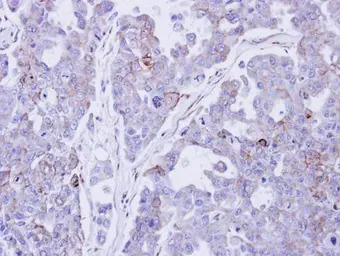

Immunohistochemical analysis of paraffin-embedded OVCAR3 xenograft , using Desmocollin 2 (GTX108888) antibody at 1:500 dilution.

Antigen Retrieval: Trilogy™ (EDTA based, pH 8.0) buffer, 15min